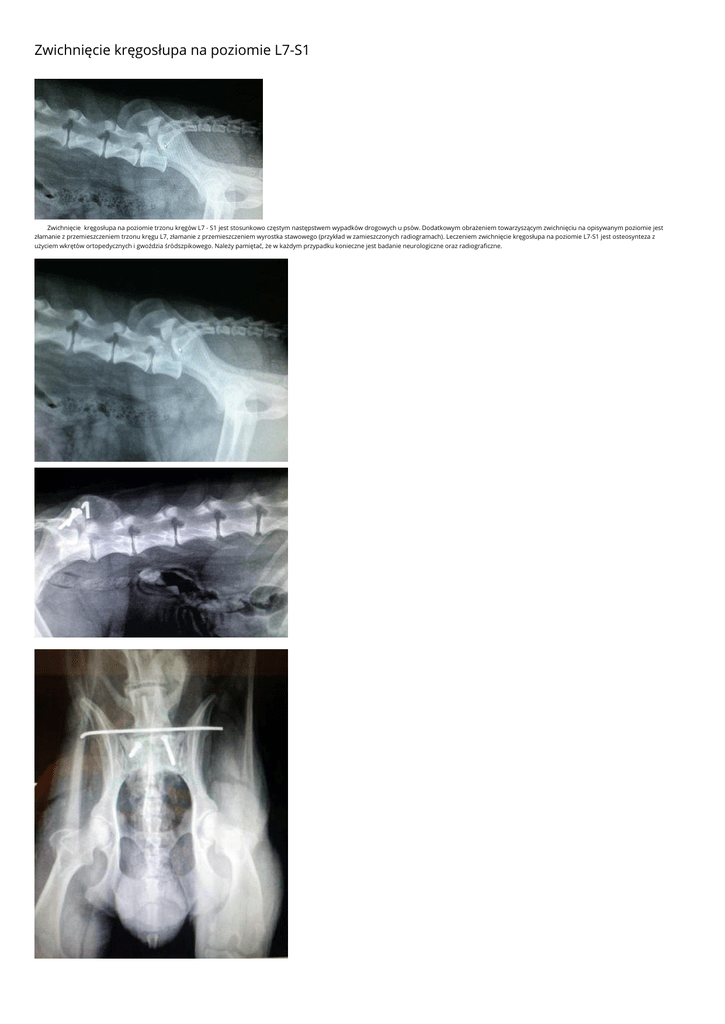

Zwichnięcie kręgosłupa na poziomie trzonu kręgów L7 - S1 jest stosunkowo częstym następstwem wypadków drogowych u psów. Dodatkowym obrażeniem towarzyszącym zwichnięciu na opisywanym poziomie jest

złamanie z przemieszczeniem trzonu kręgu L7, złamanie z przemieszczeniem wyrostka stawowego (przykład w zamieszczonych radiogramach). Leczeniem zwichnięcie kręgosłupa na poziomie L7-S1 jest osteosynteza z

użyciem wkrętów ortopedycznych i gwoździa śródszpikowego. Należy pamiętać, że w każdym przypadku konieczne jest badanie neurologiczne oraz radiograficzne.